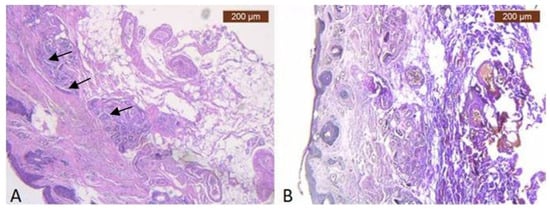

Figure 1. (A) Continuous musculo-adipose-fibrous network sending several extensions to the dermis (HE × 2.5); (B) Distinct fibro-adipose layer (VG × 2.5).

Figure 3. (A) Collagen (brown arrows) and adipose cells (yellow arrows) in similar proportions to the skin in deep dermis (HE × 5); (B) Superficial facial expression muscle fibers (black arrows) and adipose lobules extends to connect with the dermis of the skin (VG × 2.5).